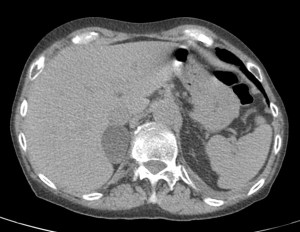

Paciente de 56 años en el que se descubre una masa suprarrenal derecha de 4,1 x 2.8 cm aprox., al realizar un TC de abdomen por otro motivo. Se procede al diagnóstico y caracterización de dicha lesión en la glándula suprarrenal derecha.

En TC son lesiones inferiores a 3 cm, homogéneas, bien delimitadas y de baja atenuación por el contenido graso que lo componen. Con contraste, como dijimos anterioremente, captan y lavan rápidamente.